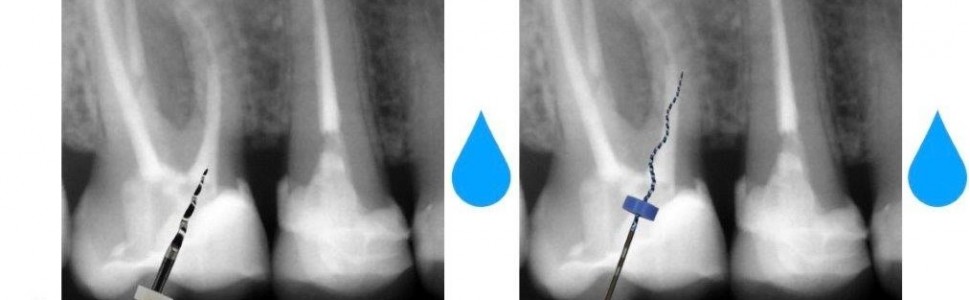

Niepowodzenie pierwotnego leczenia endodontycznego może być spowodowane przez wiele różnych czynników. Wnikliwa diagnostyka kliniczna wraz z analizą wyników badań radiologicznych pozwalają ustalić metodę leczenia rewizyjnego. W szczególnych przypadkach plan powtórnego leczenia endodontycznego można ograniczyć do wybranej części systemu endodontycznego. W artykule przedstawiono przypadek selektywnego powtórnego leczenia endodontycznego pierwszego zęba trzonowego górnego prawego z rzadko spotykaną odmianą anatomiczną kanału policzkowego mezjalnego, który w przywierzchołkowym przebiegu rozdzielał się na dwie gałęzie.